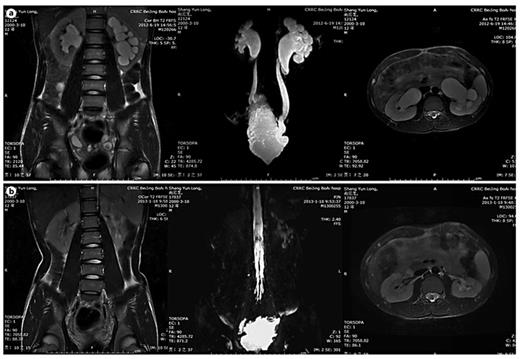

In table 1, LUTD is described according to the Guidelines of the European Association of Urology (EAU) [2] and the terminology of the International Continence Society (ICS) [5]. VUR was graded according to the IRSG, and kidney function was determined by the glomerular filtration rate from isotope renography and the serum level of creatinine. UUTD was graded as follows: grade 0, the central renal complex is closely apposed without UD (fig. 1a); grade 1, slight separation of the central renal complex exists, and the ureter is <7 mm in diameter (fig. 1b); grade 2, the renal pelvis is further dilated, a single or a few calices may be visualized and the ureter is <10 mm in diameter (fig. 1c); grade 3, the renal pelvis is dilated, there are fluid-filled calices throughout the kidney, the renal parenchyma overlying the calices has thinned (renal parenchyma loss <50%), and the ureter is tortuous and <15 mm in diameter (fig. 2a), and grade 4, similar to grade 3, but the renal parenchyma over the calices is thinned (renal parenchyma loss >50%), the ureter is severely tortuous and the ureter is >15 mm in diameter (fig. 2b). For NB patients, detrusor fibrosis and thickening secondary to progressive destruction of the bladder wall often result in ureteral strictures within the bladder wall and distal ureteral obstruction (fig. 2c), which is an important factor in the etiology of UUTD, including HN and UD, and often results in chronic renal failure. Therefore, this new system better discriminates among grade changes in UUT function, can provide objective indicators for UUT function and is an important component of long-term follow-up of conservative and surgical treatment (fig. 3).

MRU UUTD grades 3-4 and distal ureteral obstruction. a Grade 3 UUTD: MRU shows that the renal pelvis is dilated, there are fluid-filled calices throughout the left kidney, the renal parenchyma overlying the calices has thinned (renal parenchyma loss <50%), and the left ureter is tortuous and <15 mm in diameter. b Grade 4 UUTD: MRU shows that the bilateral renal pelvises are seriously dilated, there are fluid-filled calices throughout the kidneys, the renal parenchyma over the calices is thinned (renal parenchyma loss >50%), and the bilateral ureters are severely tortuous and >15 mm in diameter. c Distal ureteral obstruction: HN and UD can be displayed during 360° rotation, and vesicoureteral junction stricture or obstruction can be clearly shown (arrows: left and right ureters).

Improvement of UUTD grades by MRU after 6 months of augmentation enterocystoplasty. a Preoperative UUTD grades of right and left kidneys were 3 and 4, respectively. b Postoperative UUTD grades of right and left kidneys became 0 and 1, respectively. A significant improvement is shown.